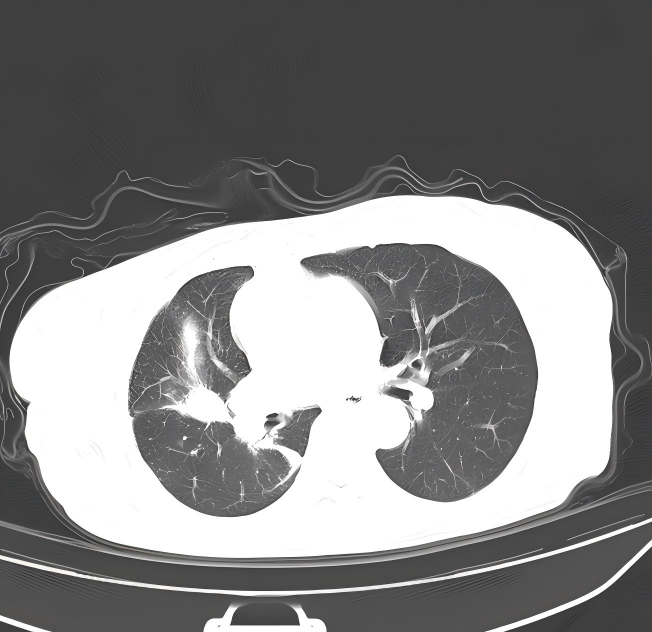

胸部+上腹部增强CT:2023.12.04我院门诊肺部CT示:1.左肺上叶结片影;右肺上叶及右肺门结块,右肺门形态增大,右肺下叶部分支气管截断,多考虑肿瘤性病变,请结合临床病史及对比前片。2.右侧胸腔积液;伴右下肺膨胀不全。3.扫及肝脏囊性灶;胆囊结石。

病理及免疫组化结果:

1.png